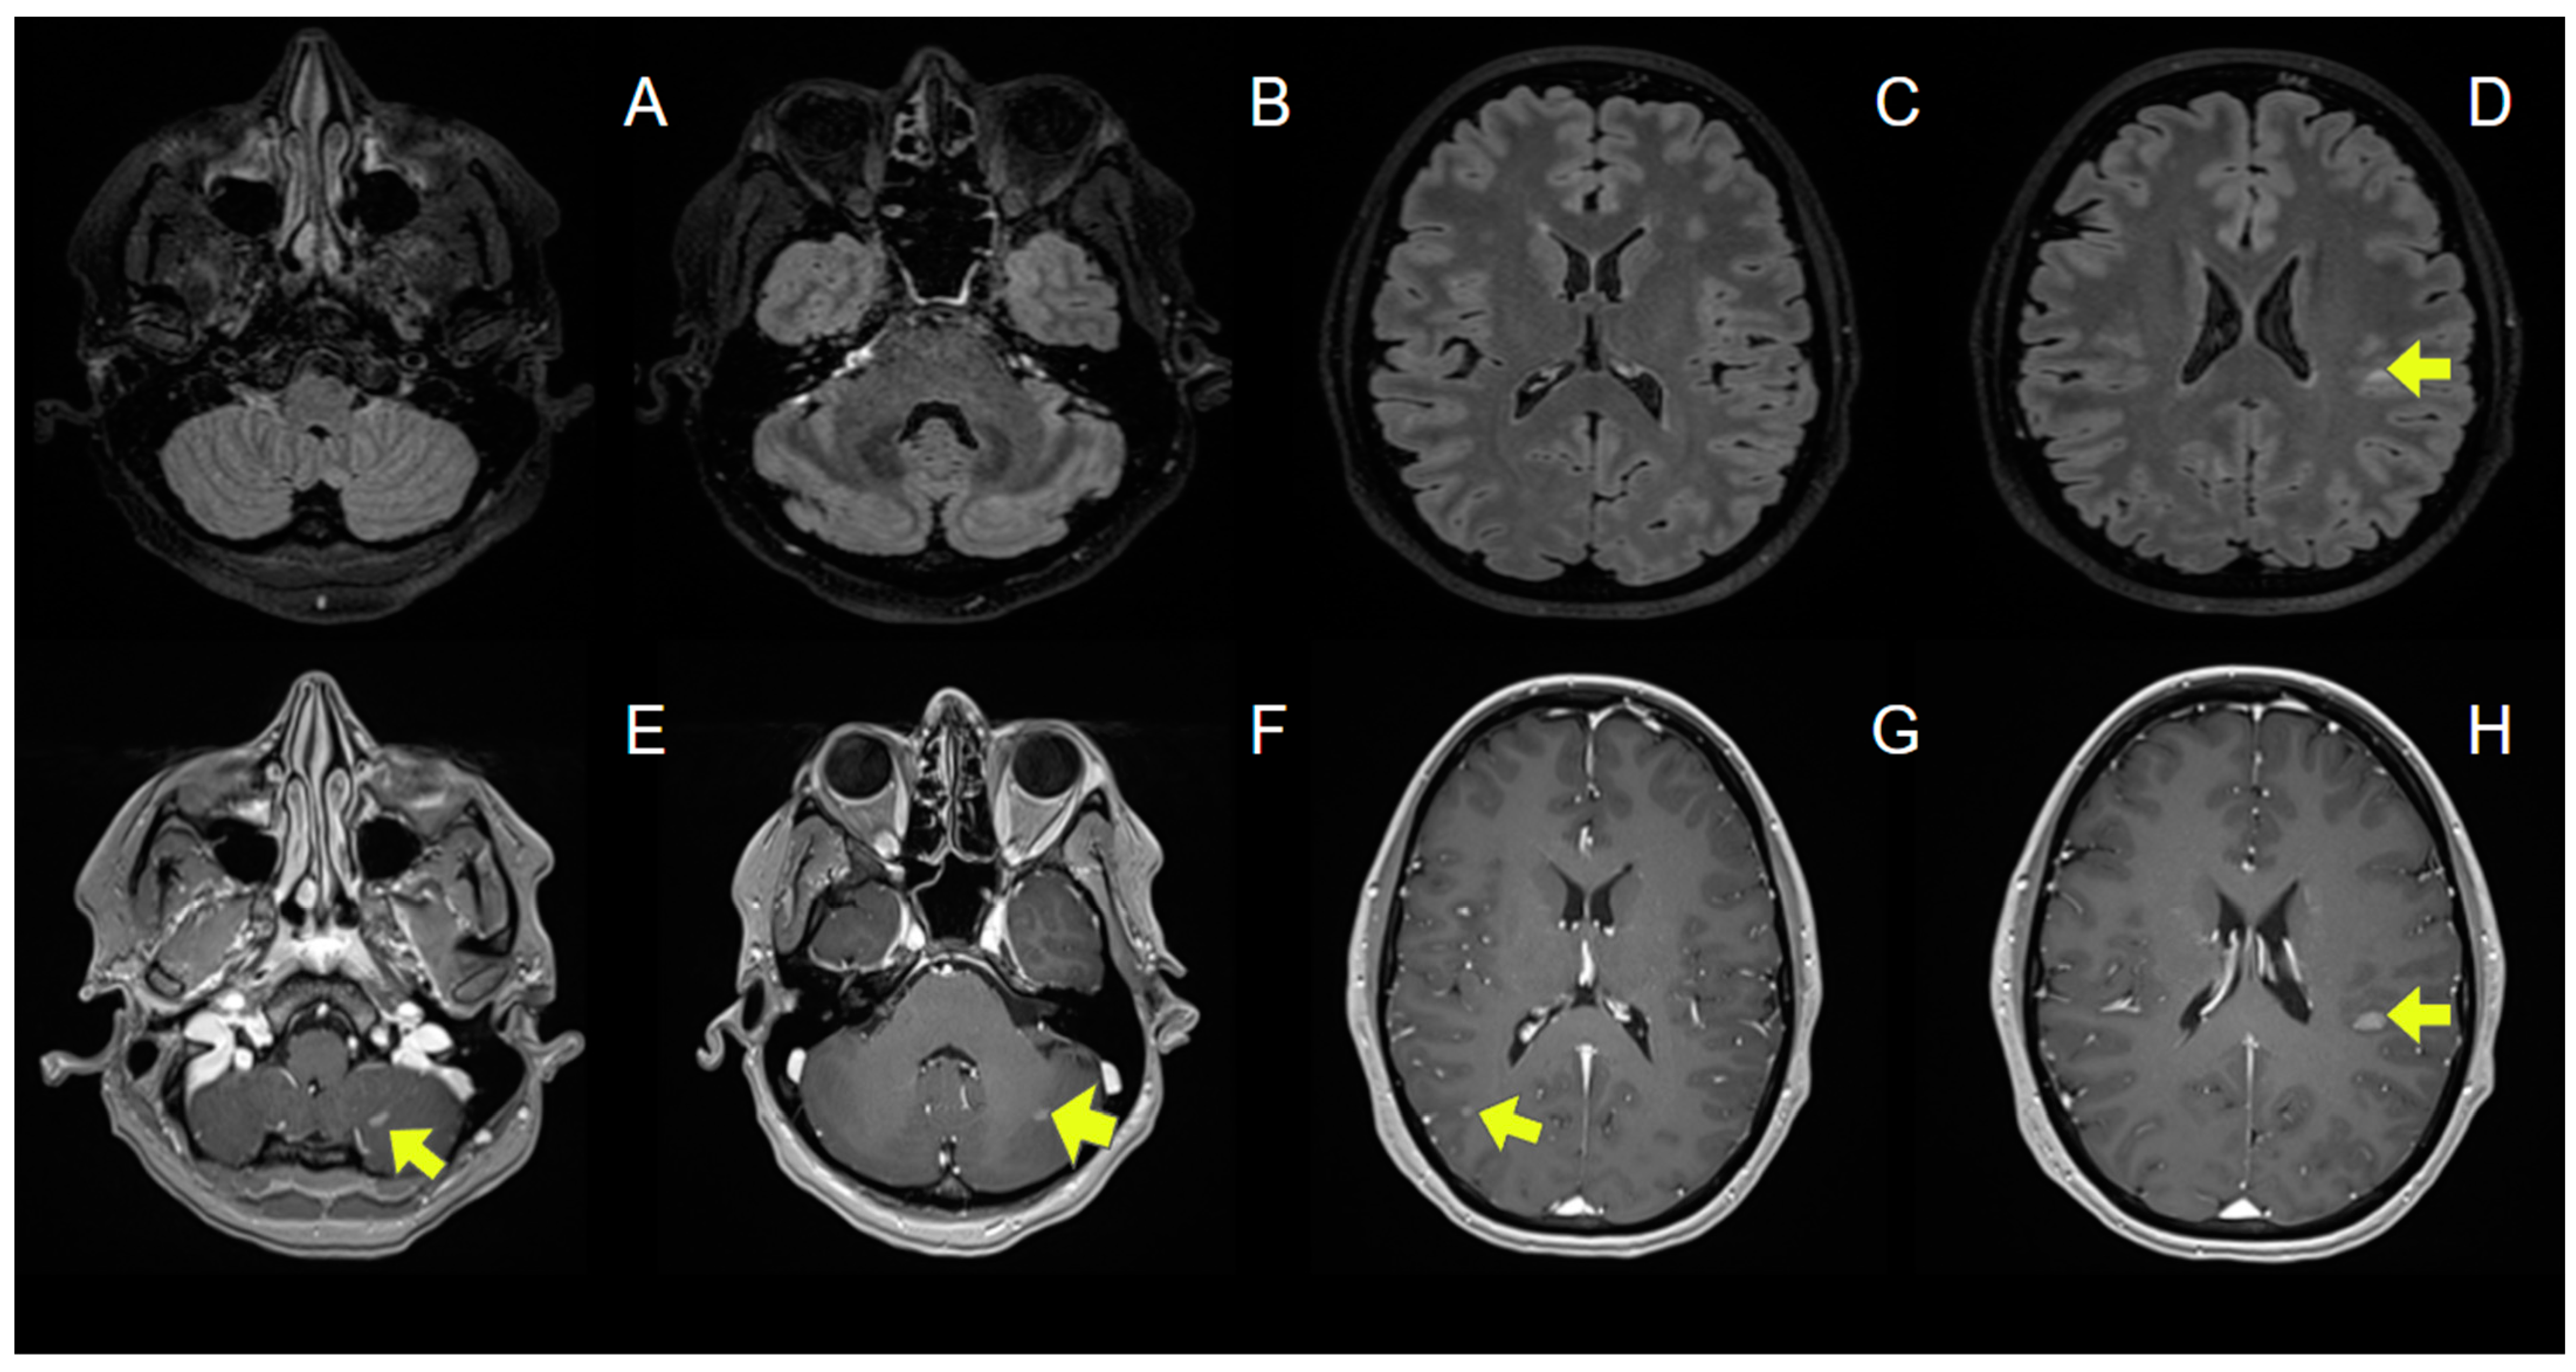

| Sterpi AE, et al. (2024) | 37/F | Breast Cancer | No | No | OLP, PLB, TRP, BVZ, LTR | IMRT | 30 | 10 | 2 months | Ataxia | Normal | No | Negative | Negative | Periventricular WM, corpus callosum, brainstem, cerebellum | - | IVMP with gradual tapering | Yes | No (6 months) | No new lesions (6 months) | N/A |